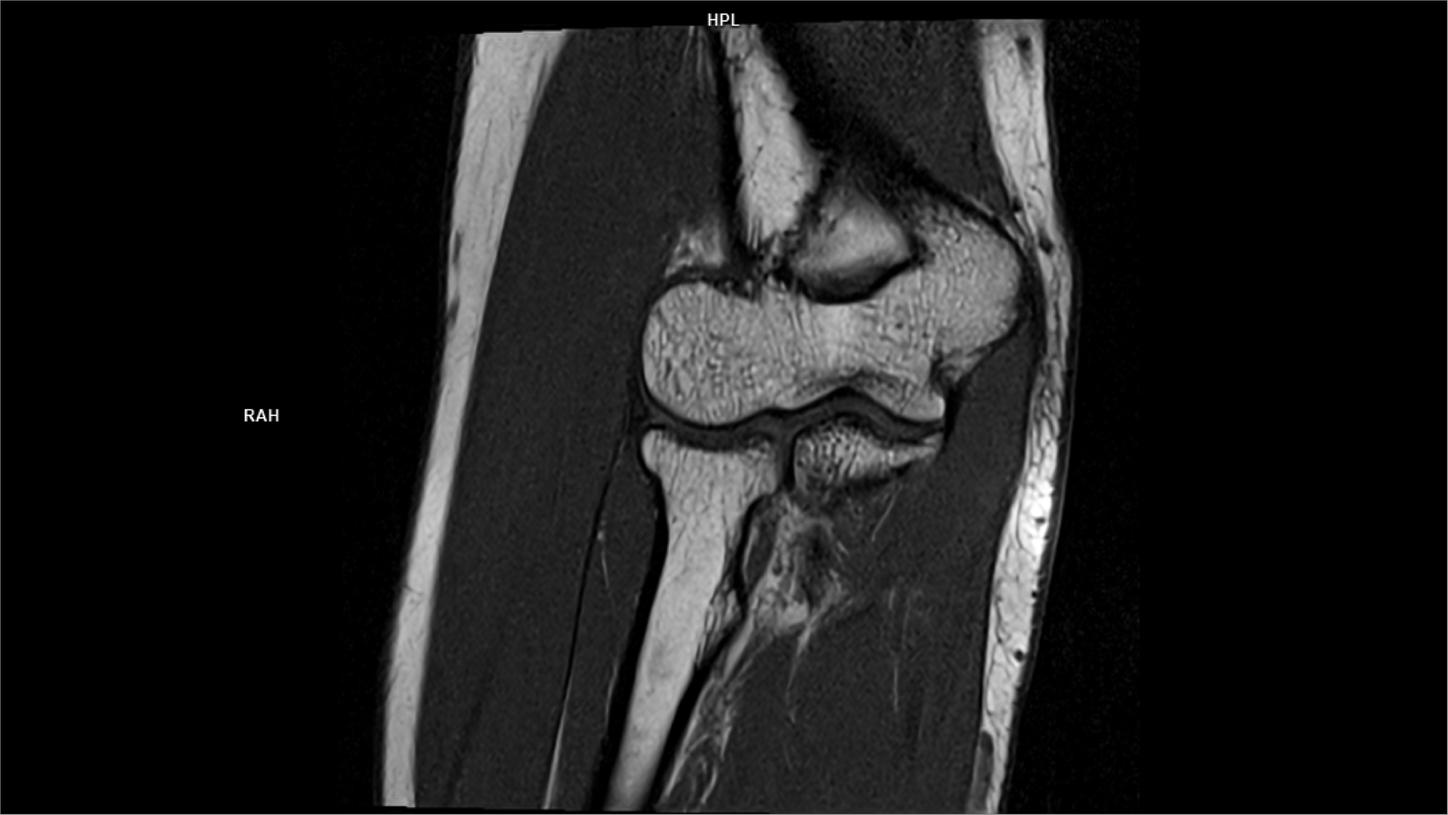

Coronal T1-MAGNETOM Free.Max